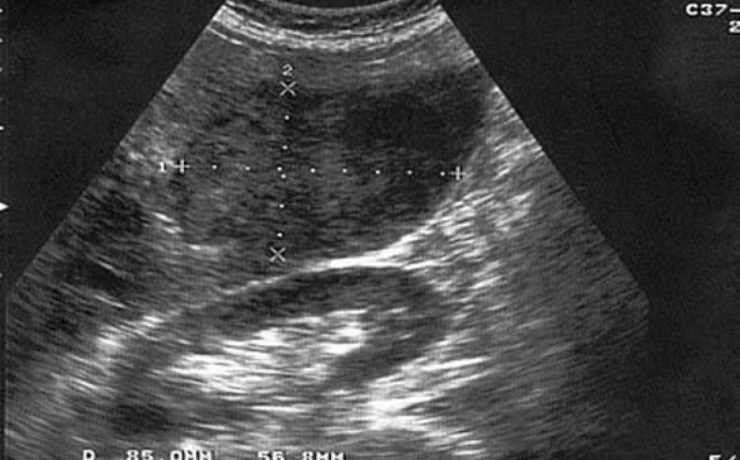

Las lesiones solidas clásicamente podemos diferenciarlas en alta, intermedia y baja celularidad. Las de alta celularidad son aquellos que poseen una gran cantidad de células, vasos edema y un rápido potencial de crecimiento e invasión. Suelen ser en la etapa inicial redondeados de bordes netos, marcadamente hipoecoicos y homogéneos, con